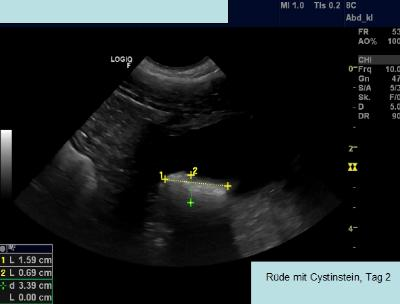

Hoewel statistische cijfers niet dramatisch lijken, is het verloop van de ziekte soms beangstigend. Als de urine verstopping niet snel wordt herkend en behandeld, kan de patiënt eraan overlijden. Daarom moet men onmiddellijk handelen als bij een urineonderzoek cystinekristallen worden aangetroffen! De snelle steen-ontwikkeling in drie dagen tijd is te volgen op de drie sonografische beelden van een aangetaste Ierse Terriër reu (Afbeelding 4a, 4b, 4c).

Foto’s van sonografische afbeeldingen van cystinesteenvorming in 3 dagen tijd, bron: eigen praktijkarchief.